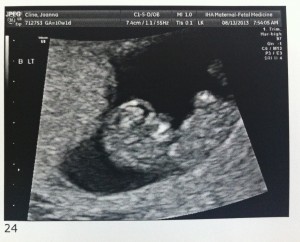

Good morning! I’m 10w1d today and we went for another ultrasound this morning. The u/s tech told us that everything looks exactly as she’d want it to at this point in the pregnancy. The heartbeats are great and they are wiggling around in there!

I’ve attached a few new photos – close ups of each and one group shot. 🙂